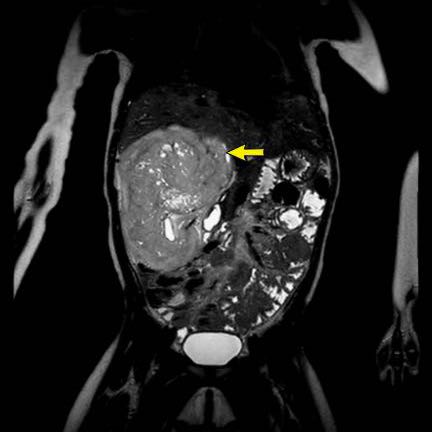

Hình ảnh chuỗi xung T2W mặt phẳng coronal cho thấy một khối u không đồng nhất ở thận trái với các thành phần nang nhỏ.

Khối u ngấm thuốc kém hơn so với phần nhu mô thận bình thường còn lại ở ngoại vi.

Các thành phần đặc của khối u cho thấy hạn chế khuếch tán rõ rệt (mũi tên).

Đây là u Wilms ở bé trai năm tuổi. Hóa trị tiền phẫu được thực hiện theo phác đồ Umbrella của SIOP-RTSG, sau đó tiến hành cắt thận.